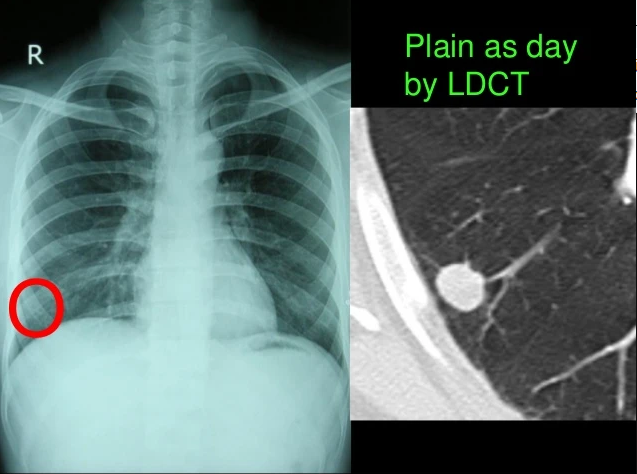

Hình 1. Hình ảnh nốt trên hình XQ và cắt lớp vi tính phổi.

Sự khác biệt của X quang phổi thường quy và chụp CLVT liều thấp